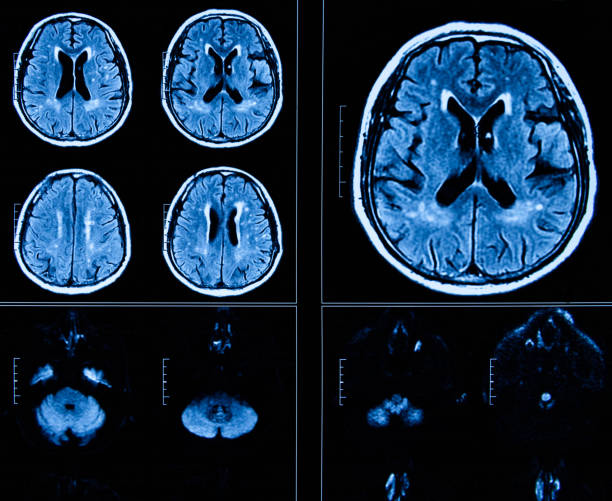

뇌졸중은 뇌출혈이나 뇌경색의 증거가 나타남과 동시에 신경학적 증상이나 신경학적 결핍 증상이 나타나면 뇌졸중으로 보는데 이에 동반하여 편마비, 사지마비, 감각저하, 감각이상, 보행장애, 언어장애, 균형장애 등 다양한 증상이 나타납니다.

뇌졸중 전조증상을 간단하게 체크할 수 있는 방법은 얼굴로 얼굴을 보고 웃거나 하는 표정을 지었을 때 한쪽에 마비가 있거나 표정이 잘 지어지지 않고 음식을 섭취했을 때 음식이나 물을 한쪽으로 흘리는 양상이 나타나면 뇌졸중으로 의한 안면마비일 가능성이 높습니다.

뇌졸중 전조증상 확인할 수 있는 다른방법은 양쪽 팔을 들어 보는 방법으로 팔을 들었을 때 한쪽 팔이 중력을 이기지 못하고 아래로 떨어지거나 한쪽 팔이나 다리에 감각이 조금 무뎌지는 느낌이 든다면 이역시 뇌졸중으로 인한 마비 혹은 감각저하를 의심할 수 있습니다.

세번째 뇌졸중 전조증상 체크 방법은 언어로 대화를 할 때, 다른 사람들이 잘 알아듣지 못 할 정도로 어눌한 말투를 쓴다거나 타인이랑 서로 대화를 할 때 횡설수설하거나 대답을 잘 하지 못한다면 이역시 뇌졸중 증상을 의심할 수 있습니다.